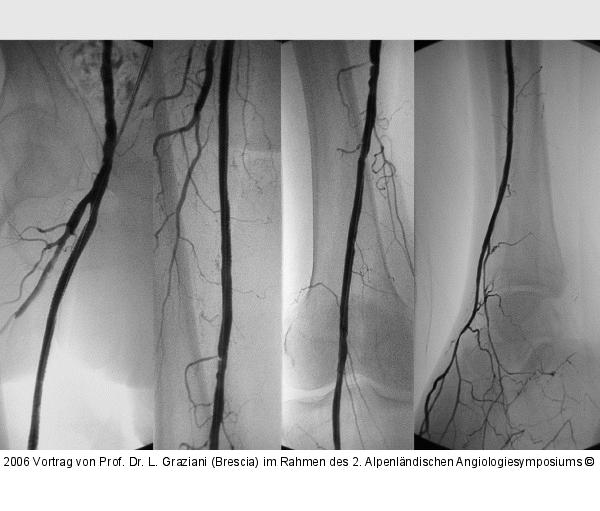

Vortrag von Prof. Dr. L. Graziani (Brescia) im Rahmen des 2. Alpenländischen Angiologiesymposiums

PTA of the foot arteries in diabetics: Extremities Extreme Angioplasty

Abbildung 39: PTA